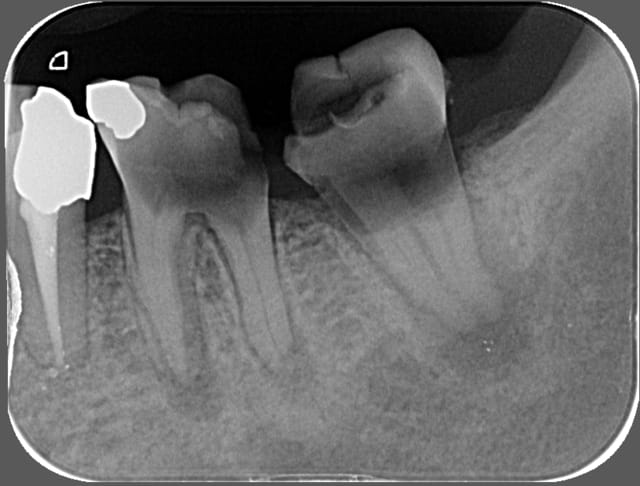

Jeune fille 14s 10mois se présente au cabinet en urgence pour douleur secteur 3.

En bouche: abcès fistulisé vestibulaire en regard de 36. Couronne extremement délabré. 46 Dans le meme état mais pas d'abcès.

Pas de 37 ni de 35 en bouche. Les autres 7 et 5 sont présentes.

Devenir de la 37? va t'elle faire son éruption? Ou est-elle morte dans l'oeuf?

Pour moi le pronostic est compromis par l'atteinte furcatoire pas pour la difficulté de bien réussir ton endo !!

Ne t'inquiète pas pour la 37 qui est parfaitement saine et qui fera son éruption normalement.

Pour 36 si tu as de la motivation et de la coopération en quantité cela se tente. Les lésions fistulisées répondent bien à l'endo, les foyers fermés un peu moins. Tu auras à gérer la limite mésiale de la cavité de carie qui est très basse.

Il est inutile de faire subir de longues séances de soins à un patient qui nous annonce dès le début (de façon implicite) qu'il n'ira pas au bout du traitement. La 37 est très immature pour presque 15 ans et n'aura pas trop de mal à se mettre en place de 36, spontanément. La furcation du germe de 37 est à peine minéralisée. Y a-t-il un germe de 38?

Il n'y a pas s'énerver avec un parage dans le pus (car, à en juger par la radiographie, il n'y a plus de sang et la pulpe est en état de liquéfaction) ça n'est pas si terrible.

À 14 ans les molaires ont des canaux qui ne sont pas difficiles à localiser et leur diamètre est trés large, cela ne devrait pas être très long de débrider, d'irriger, de sécher, de placer un Ca(OH)2 et une obtuation provisoire. L'hydroxyde devra probablement être changé une fois par semaine pendant quelques temps.

J'ai obturé et on va bien voir le resultat...Je préfère tenter le coup! Si ça marche pas tant pis, mais j'ai vu des cas avec des lésions similaires guérir ad integrum. La taille de la lésion si elle est strictement d'origine endo ne me parait pas être un facteur de pronostic de reussite du traitement.

p.s. oui je sais je dépasse en mésial :(